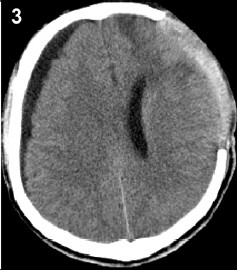

2.4 HydrocephalusPosttraumatic hydrocephalus (PTH) has a high incidence among patients with severe head trauma (Figure 4). Most PTHs are communicated hydrocephalus, which resulted from the disorder of CSF circulation. Commonly,the PTH is considered as a DC complication when it accomplishes the following conditions: onset within 6 months after head trauma, dilation of ventricles not caused by brain atrophy according to CT scan and neurological deterioration or lack of improvement is observed[16]. In Choi’s study, the PTH had an incidence of 4% among 693 patients following head trauma,but in the same series there was a quite high incidence of 23.6% among 55 patients who underwent DC[17]. We also reported a high incidence of PTH (29.4%) among 108 patients,and in our study,and PTH is also the most frequent complication during the first month following DC[2]. At present a number of studies suggested that DC probably aggravates such CSF circulation dysfunction, and increases the inscidence PTH.

| Figure 4 A typical CT image of PTH in which the lateral and third ventricles are dilated is showed. |